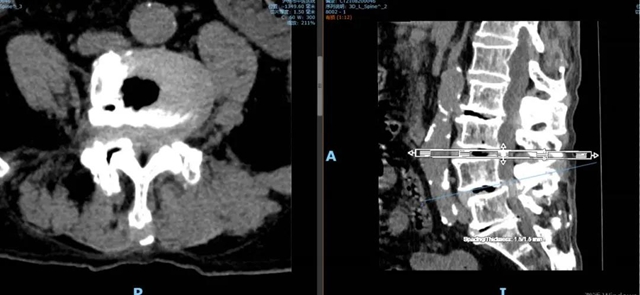

腰4 5 椎间盘CT